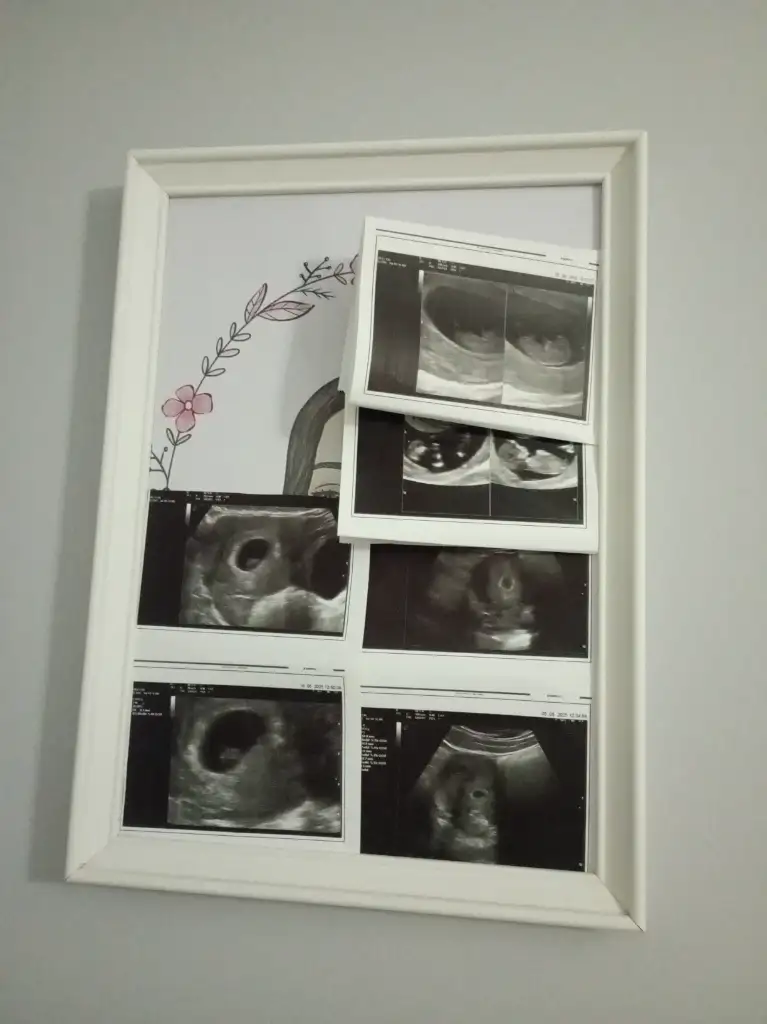

Bana da bakar mısınız lütfen biri 9 haftalık biri 6 haftalık karından ultrasonKese şekline göre erkek bence. Sağlıkla kucağınıza alın

Banada bakar mısnız lütfennnn çok merak ediyorum biri 9 haftalık biri 6 haftalık ultrason karından

Nuba göre ankıyormusunuz acaba?Bariz görünüyor kız diyorum

Erkek bence. Sağlıkla kucağınıza alınBana da bakar mısınız lütfen biri 9 haftalık biri 6 haftalık karından ultraso